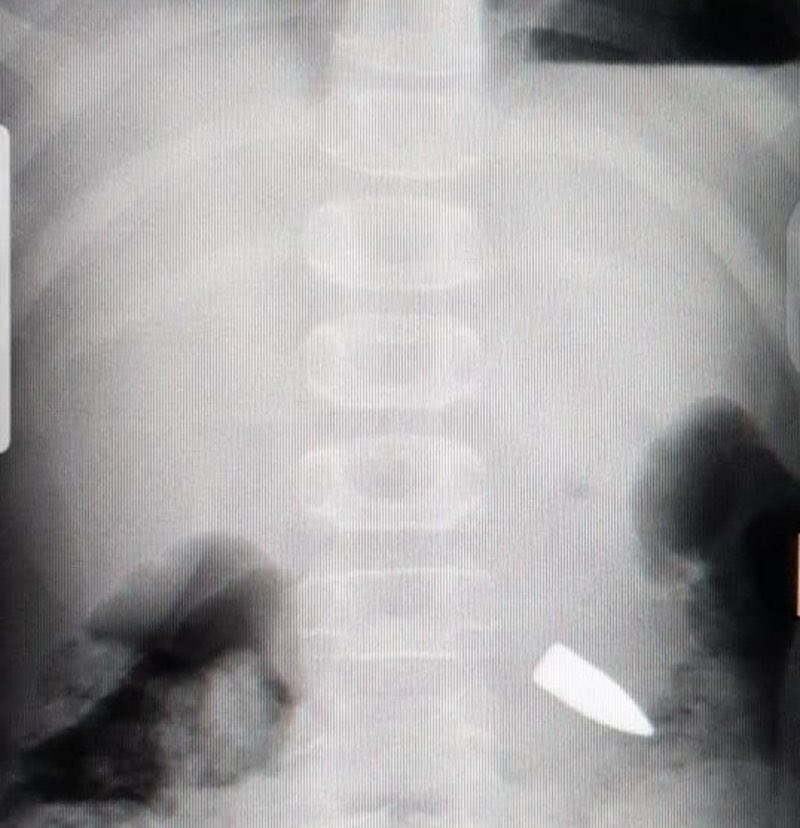

حسبنا الله ونعم الوكيل في هالبهايم الي مو راضية تفهم وش معنى سلاح ، عليهم لعنة الله وش ذنب الطفل يتعرض لمثل هذه التجربة.